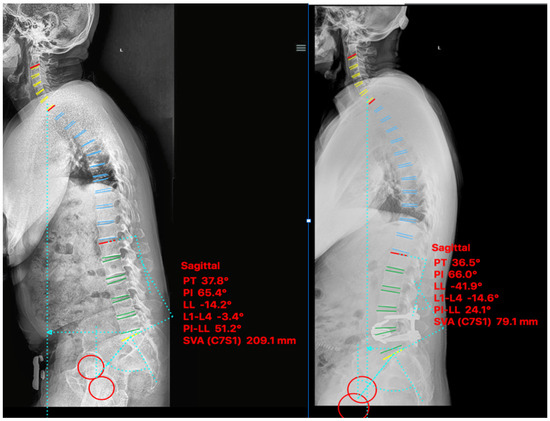

2.4.1. Case I

2.4.2. Case II